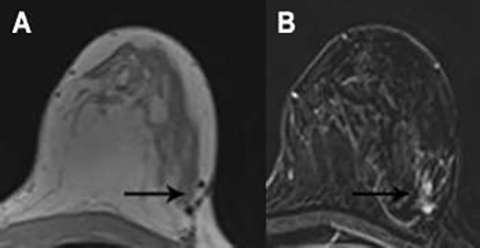

The normal appearance following mastectomy is dependent on the type of reconstruction techniques include autologous tissue flaps and implant reconstruction. Autologous tissue flaps include the transverse abdominis myocutaneous (TRAM) and deep inferior epigastric perforator (DIEP) flaps, although numerous other techniques exist. In general, post-surgical changes such as seromas and fat necrosis will also be encountered following mastectomy as in breast conservation surgery. Recurrences are most common in the anterolateral breast and axilla, where residual breast tissue may remain (Figure 6)6,7

Figure 6: T1-weighted post contrast image with fat saturation. Previous mastectomy with implant reconstruction. Enhancing masses are seen in the axilla and in the anterior breast, the latter of which extends to the nipple-areolar complex. Biopsy demonstrated recurrent breast cancer.